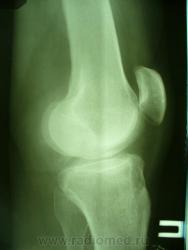

Уважаемые коллеги. Не так давно на странице сайта обсуждалась тема гипердиагностики ДОА. Хотелось бы увидеть ваше мнение по поводу наличия/отсутствия ДОА на представленных снимках. Лет 8 назад попал в автодорожку где-то в другом регионе, там же лечился в НИИТО (со слов, т.к. документов никаких нет) и там же наблюдался с DS: ДОА правого к/с IIст. Переехал в наш регион и решил пройти МСЭК для получения группы инвалидности. Снимки перевернуты, чтобы скрыть маркировку. Так есть ли ДОА?

Латерализация обоих надколенников, мелкий остеофит по верхнему краю правого надколенника, вытянутость и заострение межмыщелковых отростков левой б/б кости.

Вот что хотелось бы уточнить---а что это у нас с межмыщелковыми возвышениями справа???? а что это за окостенение по наружному контуру латерального мыщелка бедра??? ТРАВМА В АНАМНЕЗЕ!!!! Так что - справа - норма? Извините - не уверен. Група не только по снимкам определяется...функция тоже учитывается. А если сделать пару снимков для оценки межмыщелкового углубления и этих самых возвышений.

Выбирай, не выбирай..., а получается только гетерогенное окостенение у внутреннего надмыщелка правой бедренной кости. А с инвалидностью? Косинская как раз и работала в Ленинградском институте экспертизы трудоспособности инвалидов: 2 ст. = 2гр., 3 ст. = 1 гр., в данном случае - никакой группы. Молодцы травматологи, вылечили человека в НИИТОУлыбаюсь!

А почему так явно сточены межмыщелковые возвышения справа,  и вопрос: раз рядом с коленом палец - значить его придерживали, или может вообще фиксировали, как палец оказался на снимке? Последнее могло повлиять на рентген картину.

Все правильно замечено. Это, конечно не пальцы, а дополнительные фрагменты костной структуры. Была травма, больной лечился в ИТО. Вероятно, это окостеневшие фрагменты связок, хряща или чего там еще. И межмыщелковое возвышение "изгрызано", м.б. был перелом верхушек. Но ведь это все это не является R- признаками ДОА. Цель демонстрации - выяснить, есть ли рентгеновcкие признаки обезображивающего остеоартроза?